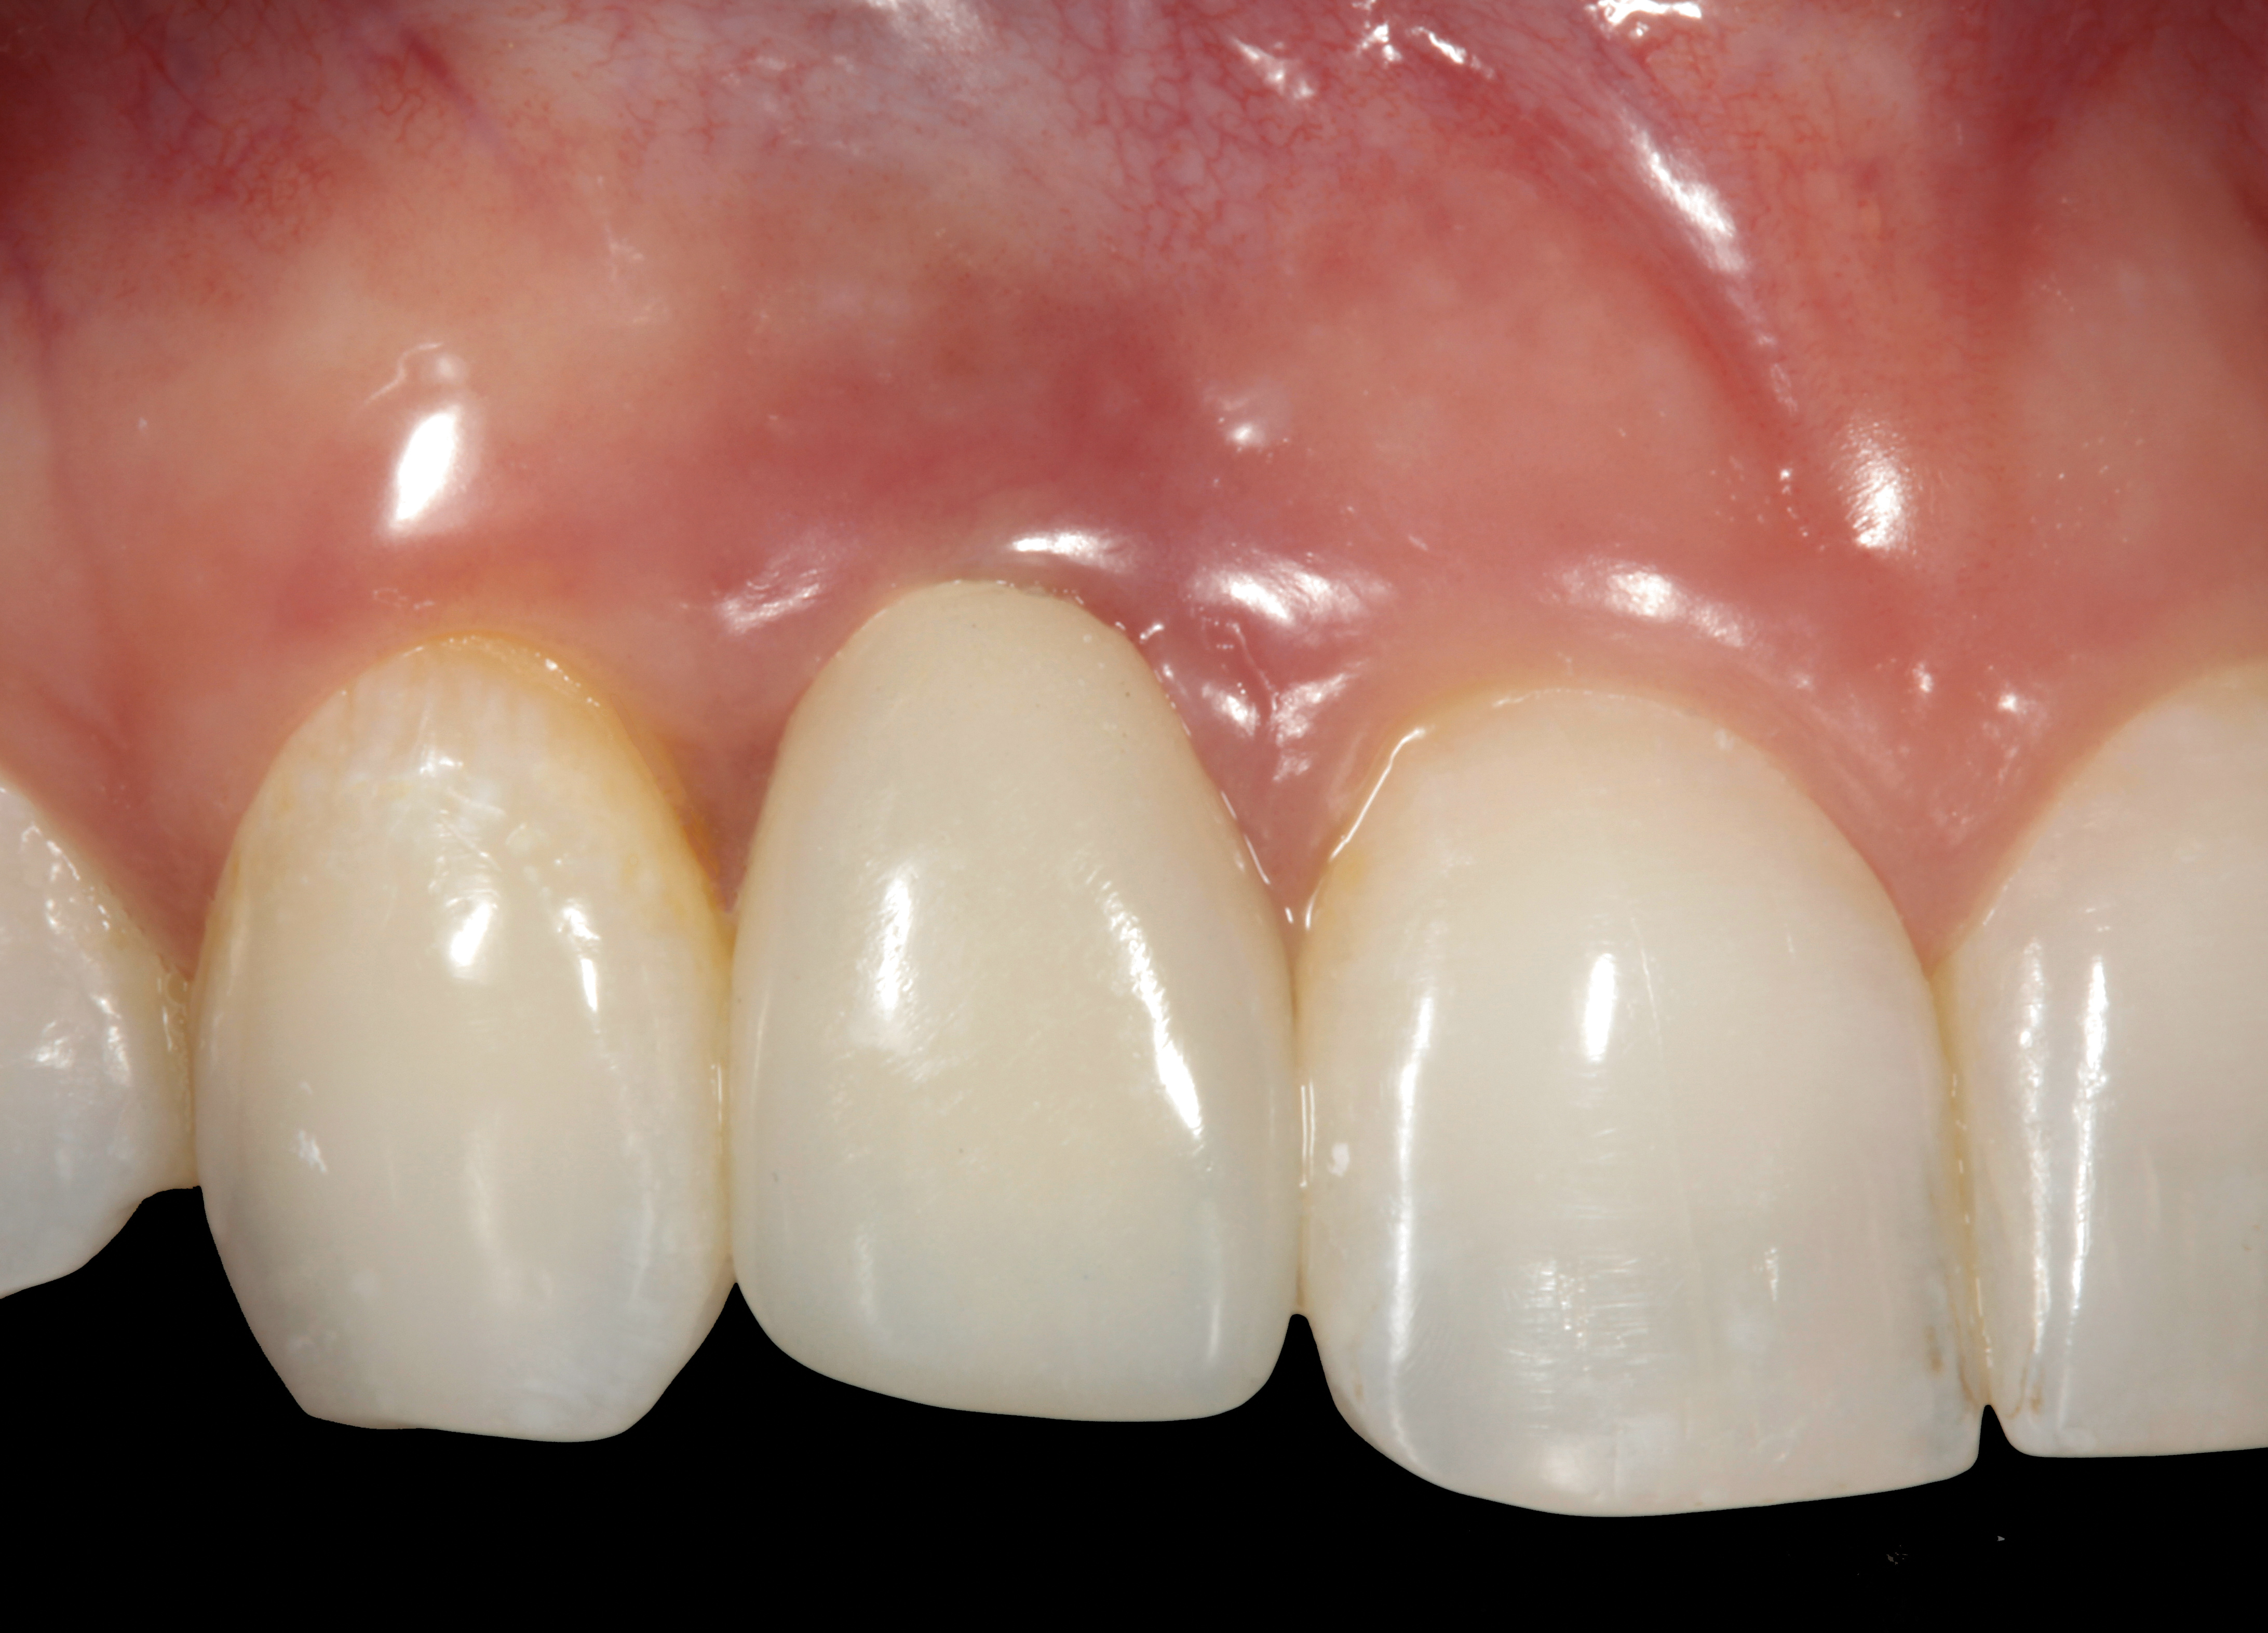

The following case report provides an example of this case scenario: A 28-year-old white female patient presented with her maxillary right lateral incisor significantly longer than the contralateral tooth following restoration of an existing crown that was 10 years old (Figure 3). The patient was dissatisfied with the esthetic appearance of the restoration due to the increased length, recession of the gingival tissues, and discoloration of the surrounding mucosa (Figure 4). Similar to case scenario No. 1, the first step in treatment was to decoronate the healthy implant by placing a flat surgical cover screw and employing a provisional resin-bonded-retained (RBR) prosthesis as a transitional fixed restoration (Figure 5 and Figure 6). The gingival augmentation in situ was allowed to take place for 2 to 3 weeks and was evaluated after that time (Figure 7).

It was determined that additional augmentation was required to increase the soft-tissue volume, so a subepithelial connective tissue graft was acquired from the palate (Figure 8),23,24 placed, and allowed to mature for at least 3 months. Second-stage implant undercovering surgery with a palatal-biased incision was performed after tissue maturation to further thicken the labial soft tissues. In addition, a flat contoured healing abutment was placed to allow the soft tissues to mature without risk of recession, and the RBR replaced (Figure 9). After 4 to 6 weeks of healing, a flat contoured screw-retained provisional restoration was inserted (Figure 10) with the proper submergence profile to restoratively sculpt the soft tissues. An implant-level impression was made and the definitive cement-retained metal-ceramic restoration fabricated and inserted (Figure 11 through Figure 13). The final esthetic outcome to restore the proper length and proportion of the right lateral incisor to match that of the contralateral incisor was accomplished using the treatment steps outlined above, where the mucosal tissues were augmented after implant decoronation (Figure 14).

Fig 3. A patient presented with a high smile line and midfacial recession of the maxillary right lateral incisor as evidenced by the increased tooth length compared with the contralateral lateral incisor.

Figure 3

Fig 4. Intraoral view of tooth No. 7 with the gingival zenith more apical than the adjacent central incisor and canine tooth.

Figure 4